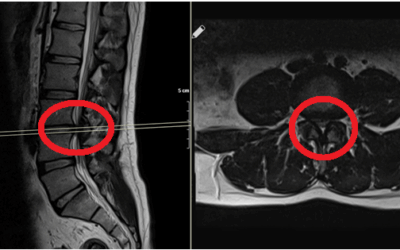

Bel Fıtığı (Lomber Disk Hernisi)

Bel Fıtığı Nedir? Bel fıtığı, omurlar arasında yer alan ve amortisör görevi gören disklerin, dış çeperinin zayıflayıp yırtılması sonucu iç kısmındaki jel benzeri yapının dışarı çıkmasıdır. Bu dışarı çıkan doku, sinir köklerine baskı yaparak ağrı, uyuşma ve güç...